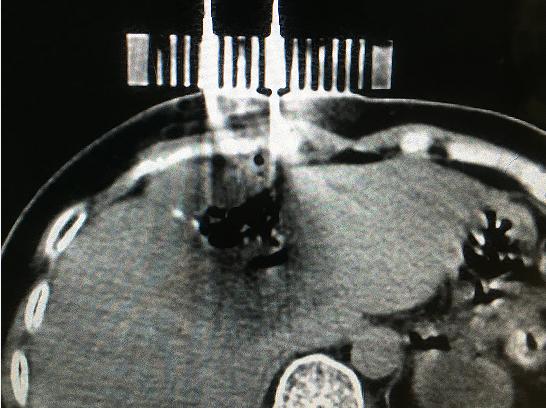

9月11日,醫(yī)院腫瘤科張開賢主任醫(yī)師團隊對一例肝癌術(shù)后復(fù)發(fā)的患者成功進行了國內(nèi)首例3D打印共面模板引導(dǎo)下的微波消融術(shù),標(biāo)志著肝癌進入精準(zhǔn)微波消融時代。

患者女性,57歲,肝癌術(shù)后5月復(fù)發(fā),病灶6.0cmx6.0cm大小,位于肝臟的右葉,靠近隔頂部,經(jīng)過多學(xué)科討論,決定實施經(jīng)皮微波消融術(shù),由于腫瘤體積較大,需要同時使用兩根消融天線進行多平面消融,為確保療效,兩根消融天線需要平行等距,但由于肝臟是不斷運動的臟器,徒手操作有一定技術(shù)難度,往往需要多次穿刺調(diào)整進針方向才能達到上述要求,為此,滕州市中心人民醫(yī)院腫瘤科張開賢主任醫(yī)師團隊借鑒既往采用模板引導(dǎo)放射性粒子植入的經(jīng)驗,創(chuàng)造性地將3D打印模板技術(shù)應(yīng)用于該例患者的消融治療,在模板引導(dǎo)下在兩個平面上平行等距插入兩根消融天線,經(jīng)過18分鐘的消融,腫瘤完全壞死,達到完全消融,患者正在術(shù)后康復(fù)之中。

3D打印模板引導(dǎo)消融的優(yōu)點:迅速將腫瘤與模板“固定”,防止因肝臟運動導(dǎo)致的穿刺不確定性;確保兩根消融天線平行等距,使熱場分布更加均勻;一次性穿刺布針成功,避免反復(fù)穿刺導(dǎo)致的腫瘤種植性轉(zhuǎn)移;模板對消融天線起到固定,防止因來回移動導(dǎo)致的消融天線位置的改變。據(jù)悉,這是國內(nèi)首例3D打印模板引導(dǎo)下的肝癌微波消融術(shù),這一技術(shù)的推廣應(yīng)用必將造福更多的腫瘤患者。(腫瘤一科 胡苗苗)